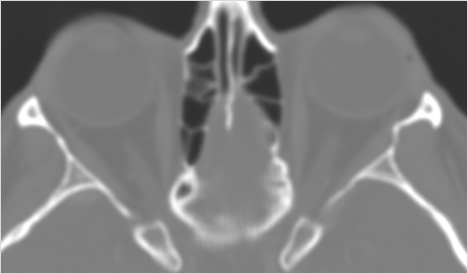

Orbits and Orbital Zygomatic Complex

The preseptal soft tissues including the lacrimal gland and sac are normal.

There is evidence of a subperiosteal hematoma along the medial or lateral wall, roof or floor of the orbit.

The circumferential extraconal and the intraconal orbital fat are infiltrated.

There is evidence of herniated intra-orbital fat.

The extraocular muscles are swollen, infiltrated or herniated into a fracture site.

There is evidence of bony injury along the walls and/or floor of the orbit.

Eyes

Proptosis is present.

There are signs of a decompressed globe.

The lens is in normal position on either side.